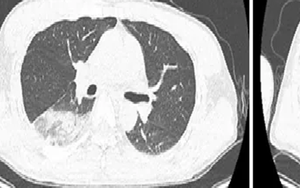

Sống khỏe 2025-11-05T20:11:00Nam bệnh nhân 46 tuổi đã sốt cao liên tục suốt 10 ngày, gan thận tổn thương nặng.

Nam bệnh nhân 46 tuổi đã sốt cao liên tục suốt 10 ngày, gan thận tổn thương nặng.